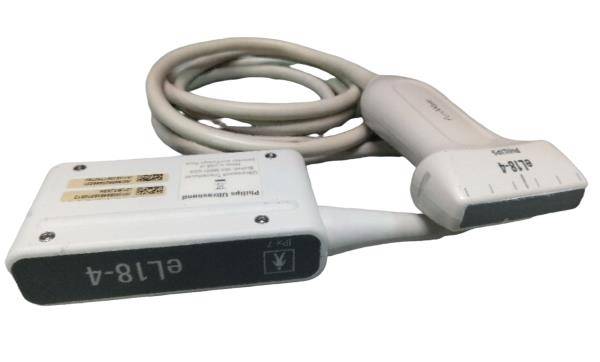

Brand

Philips

MPN

S8-3